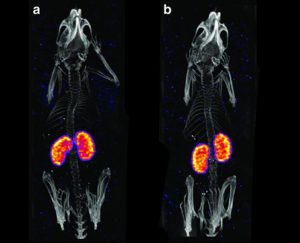

Image analysis is a critical component of clinical and preclinical imaging research, providing a means of quantifying and interpreting the data generated by imaging modalities such as PET, SPECT, and CT. In clinical imaging, image analysis is used to aid in diagnosis and treatment planning. For example, in oncology, image analysis can be used to assess the response to chemotherapy and radiation therapy, providing a means of monitoring the effectiveness of treatment and making adjustments as necessary.

In cardiology, image analysis can be used to evaluate blood flow and cardiac function, enabling the diagnosis and treatment of heart disease. In preclinical imaging research, image analysis plays a crucial role in the development of new treatments and therapies. Image analysis algorithms can be used to quantify the effects of drug treatments or surgical procedures on biological processes such as blood flow and metabolic activity. By providing a means of objectively assessing treatment efficacy, image analysis helps to optimize treatment protocols and improve patient outcomes.

The same image analysis techniques can be applied to both clinical and preclinical images, allowing for a seamless transition between research modalities. Moreover, image analysis has additional applications in clinical research, beyond the evaluation of disease progression or response to therapy. For example, image analysis can be used for radiation treatment planning to optimize the radiation dose and minimize side effects.

At our company, we provide a wide range of image analysis services for both preclinical and clinical imaging research. Our team of experts has extensive experience in conducting image analysis for various modalities, including PET, SPECT, CT, and optical imaging. We offer a comprehensive set of services, such as image registration, segmentation, quantification, and statistical analysis. We understand the importance of accurate and precise image analysis in the success of research projects, and we use state-of-the-art software and techniques to deliver reliable and reproducible results.